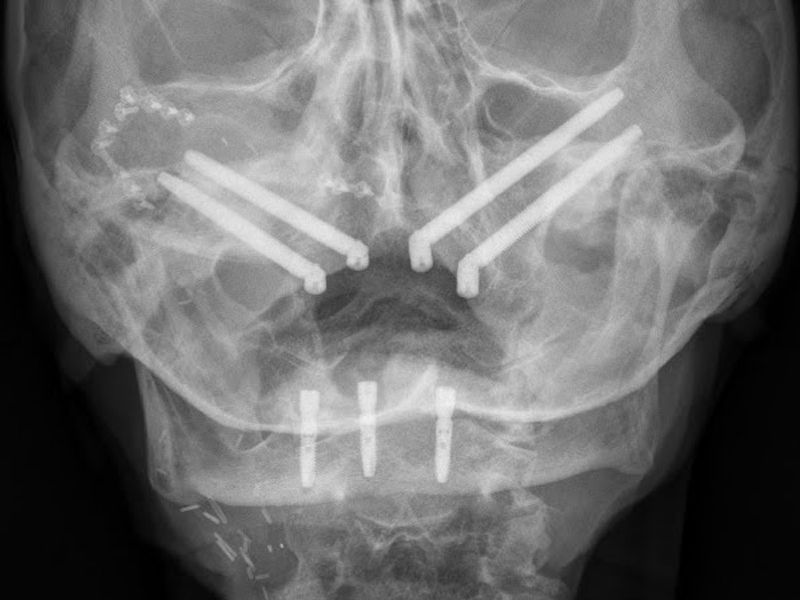

Zygomatic implants

The zygomatic implants are an excellent solution in cases of patients with little jaw bone. In this type of intervention the advantage is to be able to insert an implant without additions or regeneration of jaw bone.

Zygomatic implants can be considered aneffective alternative to bone grafting. They allow the patient to undergo the removal of any autologous bone material and therefore also to the stitches and a longer wait to have a fixed prosthesis.

Extreme precision of implant placement